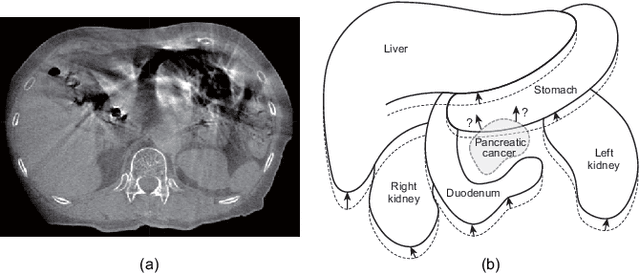

Abstract:Respiratory motion and the associated deformations of abdominal organs and tumors are essential information in clinical applications. However, inter- and intra-patient multi-organ deformations are complex and have not been statistically formulated, whereas single organ deformations have been widely studied. In this paper, we introduce a multi-organ deformation library and its application to deformation reconstruction based on the shape features of multiple abdominal organs. Statistical multi-organ motion/deformation models of the stomach, liver, left and right kidneys, and duodenum were generated by shape matching their region labels defined on four-dimensional computed tomography images. A total of 250 volumes were measured from 25 pancreatic cancer patients. This paper also proposes a per-region-based deformation learning using the reproducing kernel to predict the displacement of pancreatic cancer for adaptive radiotherapy. The experimental results show that the proposed concept estimates deformations better than general per-patient-based learning models and achieves a clinically acceptable estimation error with a mean distance of 1.2 $\pm$ 0.7 mm and a Hausdorff distance of 4.2 $\pm$ 2.3 mm throughout the respiratory motion.